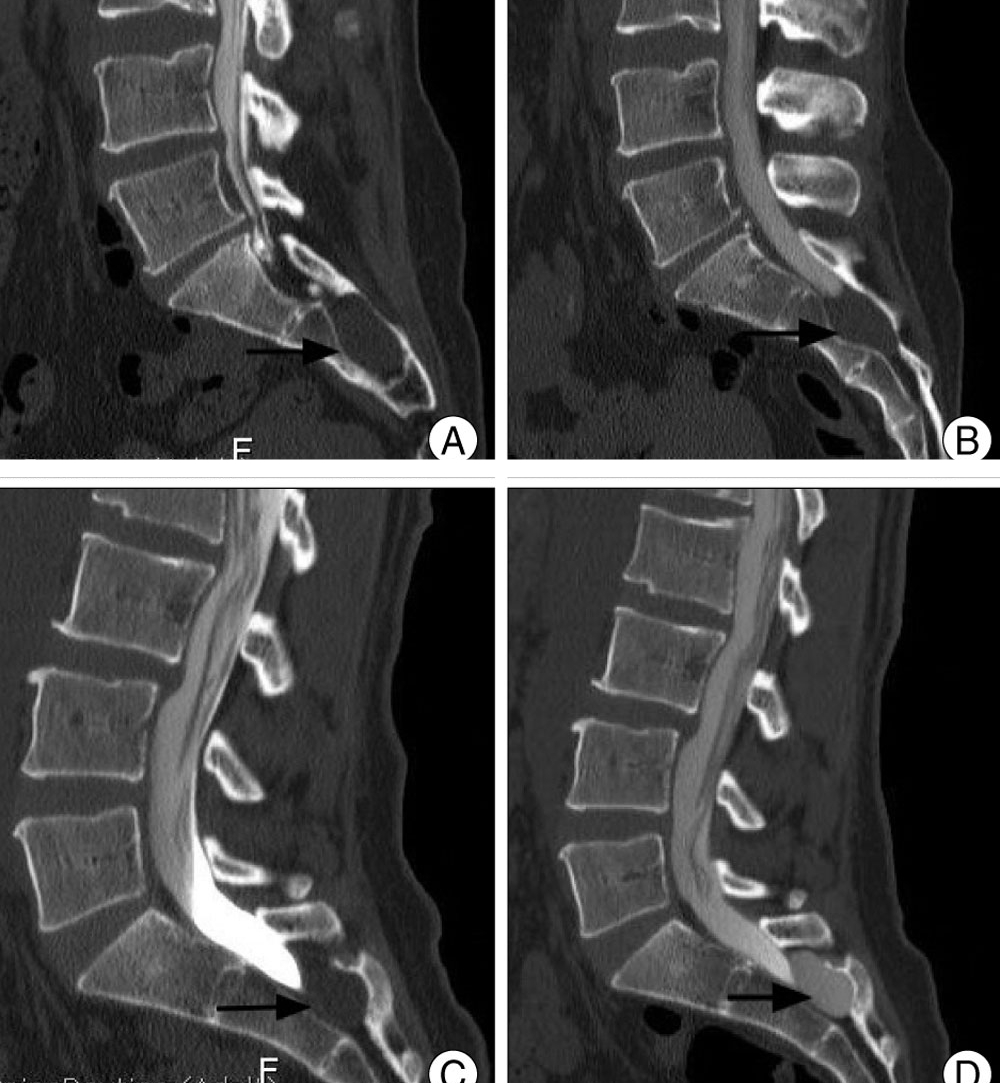

Исследование крестцово-копчиковой области также возможно с помощью компьютерной томографии (КТ), которая чаще используется при травмах копчика или повреждениях костей. МРТ назначается в случаях, когда имеются проблемы с мягкими тканями, например, воспалительные процессы.

Рентгеновский метод, хотя и позволяет получить изображения копчика, не всегда способен выявить изменения, фиксируемые МРТ, такие как старые переломы и трещины, из-за их специфического расположения. Кроме того, МРТ может обнаружить последствия травм, включая деструкции и воспалительные процессы.

МРТ позвоночника предоставляет более полную информацию по сравнению с рентгеном и компьютерной томографией (КТ), которая иногда не выявляет даже свежие травмы. МРТ позволяет получить данные о размере образований, а не только о их наличии, и обеспечивает более высокое качество изображений.

Эффективность МРТ особенно заметна при недавних травмах, сопровождающихся крупными кровоизлияниями и вывихами с разрывами связок. Также могут быть выявлены повреждения соседних костей, сосудов, сухожилий и мышц. Важно отметить, что во время работы томограф не излучает, как рентген, что позволяет проводить обследования чаще.